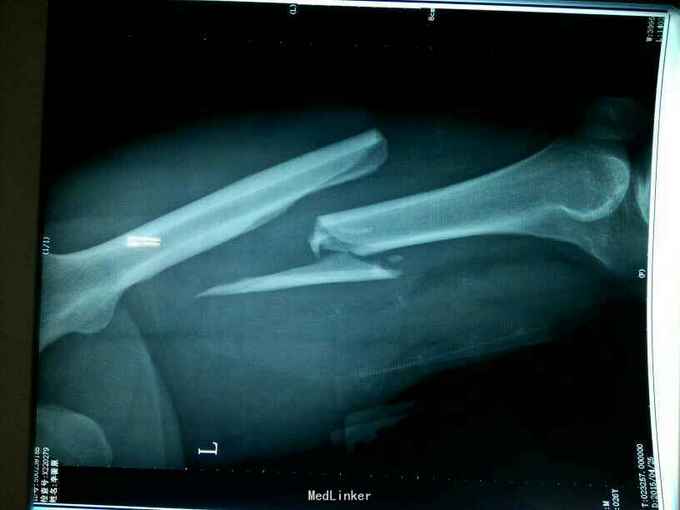

主 诉:车祸致左侧大腿部疼痛、不敢活动4天。 现病史:患者家属诉于2015年12月2车祸致左侧疼痛、不敢活动,伤后意识清,无头疼,头晕,无恶心、呕吐等不适症状,当地120急救车送至当地骨科医院,行左侧大腿正侧位提示:左侧股骨骨皮质连续性中段,断端移位明显,收入院给予左侧下肢长腿石膏外固定,并建议行手术治疗,家属要求转至上级医院诊治,今患者及家属为求进一步诊治来我院就诊,经查以“左股骨干骨折”收入院。患者目前精神尚可,体力正常,食欲正常,睡眠正常,体重无明显变化,排尿正常,大便正常。

专科情况:患者平车推入病房,左下肢石膏在固定中,拆除石膏,左大腿中段压痛、叩击痛(+),左髋关节、膝关节主动活动受限,被动活动可引起明显疼痛,骨盆挤压、分离试验(-),脊柱、余肢体无畸形及压痛、叩击痛,关节无红肿、活动自如。双侧膝、跟腱反射正常,双侧Babinski征阴性。 辅助检查:左侧大腿正侧位提示:左股骨中段骨质不连续,见多发不规则形骨折线,骨折断端错位成角,可见多发游离骨片,其周软组织肿胀。